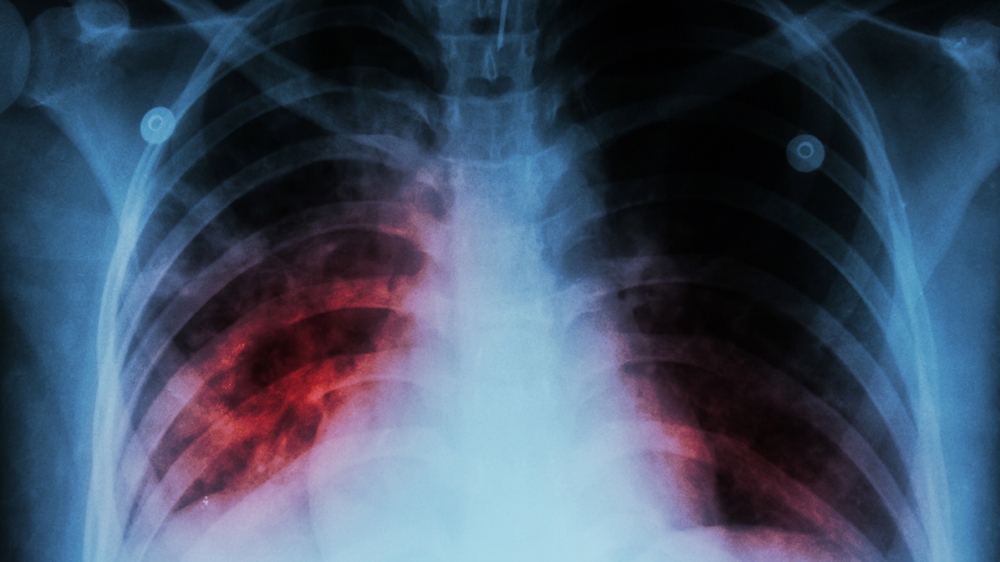

El Ministerio de Salud Pública de Corrientes confirmó que una joven de 17 años murió de tuberculosis.

De acuerdo con la información oficial, la adolescente además del diagnóstico de tuberculosis tenía “antecedentes de otra infección bacteriana”.

“La enfermedad de base era la tuberculosis pero tenía una infección agregada, lo que complicó aun más”, dijo la directora General de Epidemiología, Angelina Bobadilla.